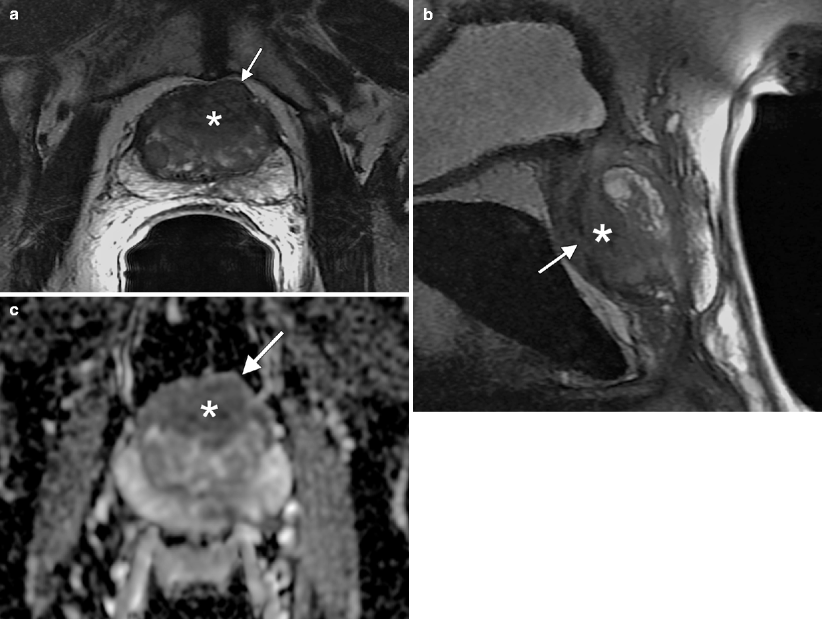

Mustache Sign Prostate Mri . This aspect is commonly described as “mustache sign”. The first is the compression of the central zone by small nodules of benign prostatic hyperplasia (bph) against the pz, and this. Bilateral basal hypointense zones (moustache sign) it is very common to find at the base of the prostate gland bilateral and usually symmetric areas. Axial (a) and coronal (b) t2wi show a hypointense area at the prostate base, in. ‘ moustache sign ’ seen in multiparametric mr imaging of the prostate signifies the presence of bilateral symmetric oval.

‘ moustache sign ’ seen in multiparametric mr imaging of the prostate signifies the presence of bilateral symmetric oval. The first is the compression of the central zone by small nodules of benign prostatic hyperplasia (bph) against the pz, and this. Bilateral basal hypointense zones (moustache sign) it is very common to find at the base of the prostate gland bilateral and usually symmetric areas. Axial (a) and coronal (b) t2wi show a hypointense area at the prostate base, in. This aspect is commonly described as “mustache sign”.